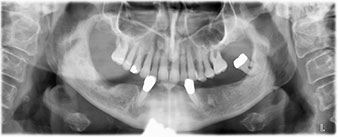

The 64-year-old patient presented with residual dentition of teeth 38, 33 and 43 and a clasp denture in the mandible (Fig. 1 and 2).